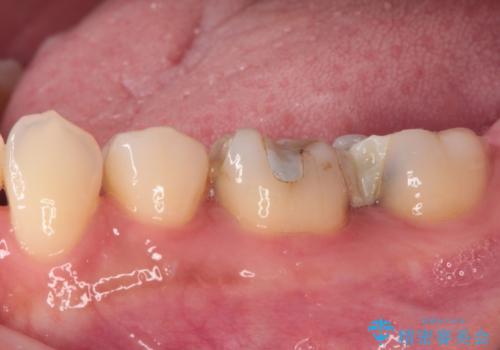

- 奥歯のむし歯処置を行っていたものの、しみて痛みが続く状態での経過観察が続いていたため、転院を希望して来院された患者様です。

痛みが続いているとのことで、むし歯が神経組織に及んでいる可能性があるため、処置を行うに当たりラバーダムによる唾液の排除を行うこととしました。